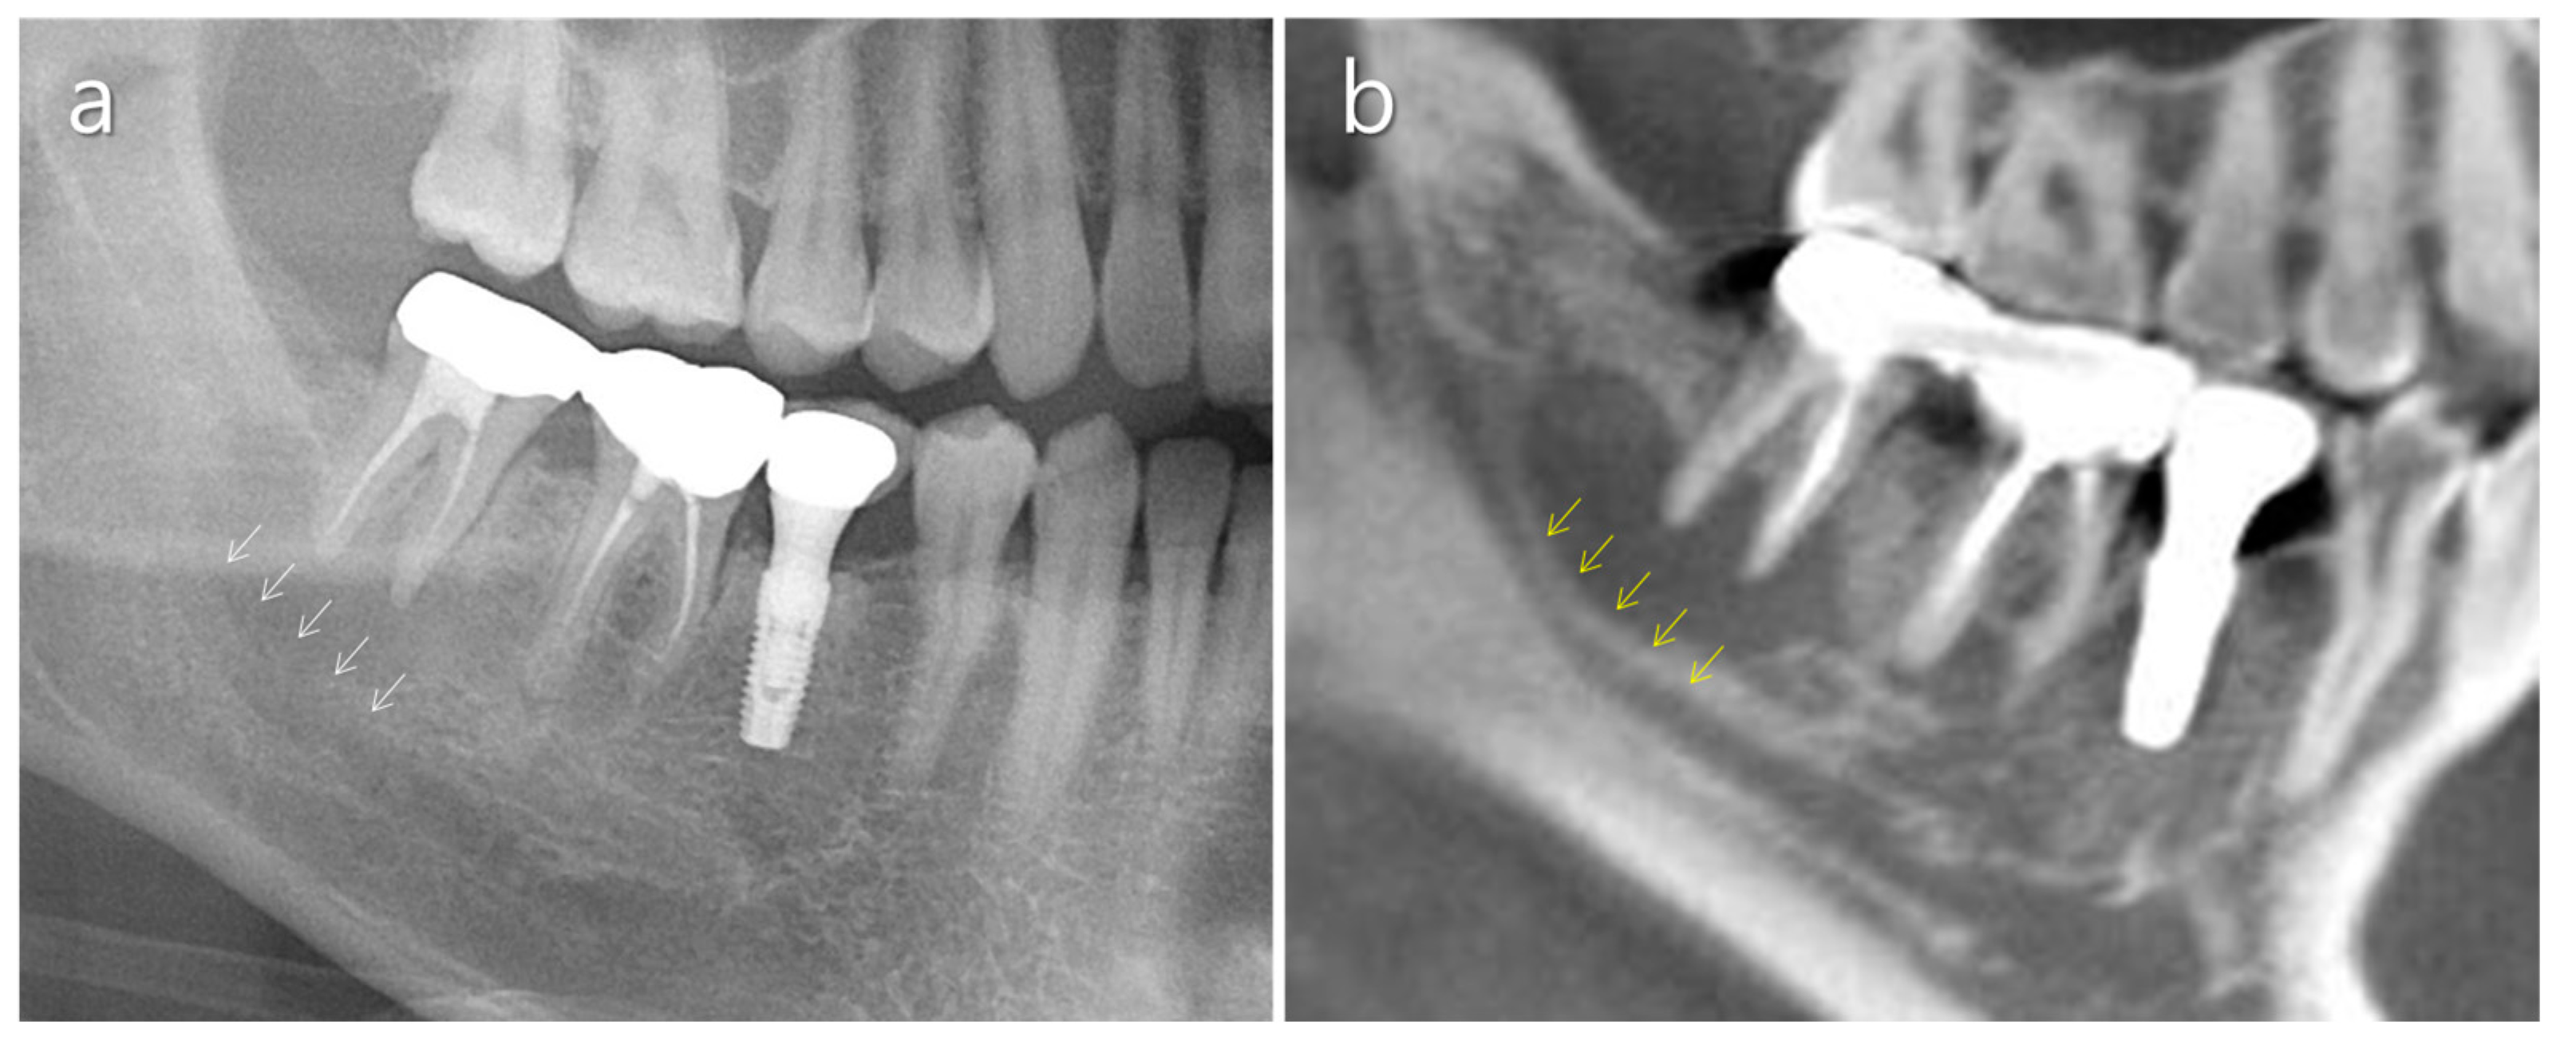

2.3. Mandibular Canal

2.4. Mental Nerve